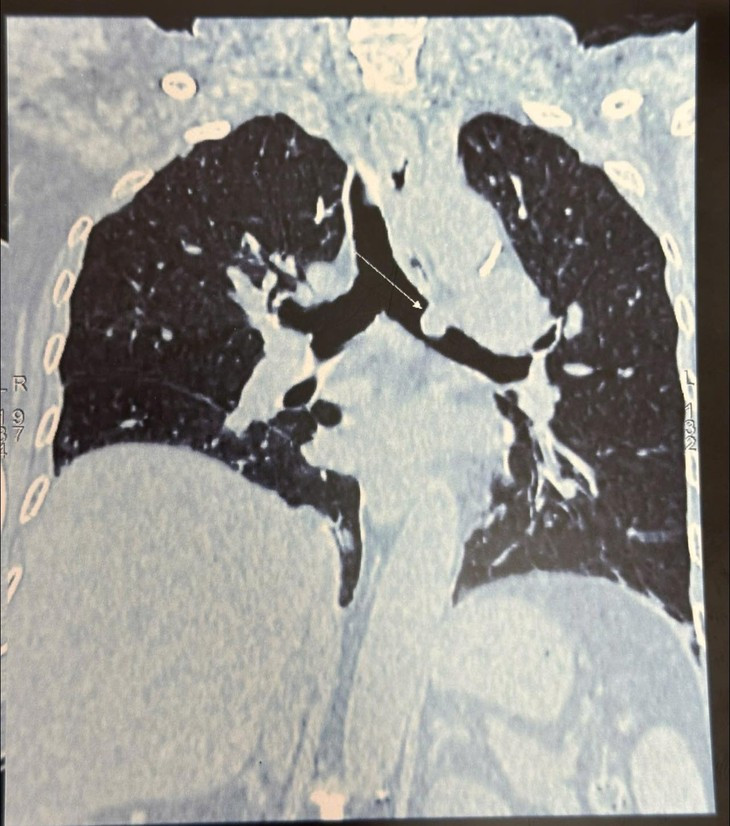

Nhận định về trường hợp này, TS.BS Nguyễn Khắc Kiểm, Trưởng khoa Ngoại lồng ngực cho biết “Khối u nằm ở vị trí phế quản gốc trái cách Carina 1cm lồi vào lòng phế quản do đó chúng tôi đã hội chẩn, nhận định phương án phẫu thuật cho người bệnh để đảm bảo hiệu quả nhất.

Xác định đây là một ca ung thư phổi giai đoạn sớm, vị trí như vậy không thể phẫu thuật cắt u theo phương pháp thông thường, đòi hỏi phải cắt, nối và tạo hình phế quản bảo tồn thùy phổi”.

| Tốn thương ung thư phổi trên phim chụp - Ảnh BVCC |

Đánh giá tổn thương trong mổ: u tại vị trí phế quản gốc trái kích thước 1cm cách Carina 1,5cm u lồi vào lòng phế quản, kíp mổ quyết định cắt đoạn phế quản gốc dài 1,5cm và nối hai đầu phế quản được cắt rời, ca mổ được thực hiện trong 3h với sự tập trung và quyết tâm cao nhất của cả ekip.